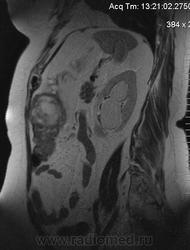

очень характерная картина для метастаза рака яичника, к сожалению.

Не могу достоверно определить локализацию метастаза брюшной полости, вероятно в лимф. узел с инвазией оободочной кишки. Рецидив С-r левого яичника думаю, что с инфильтацией левой стенки прямой кишки и культи влагалища, вторичная лимфаденопатия л/у малого таза. каликопиелоуретероэктазия (инвазия нижних отделов левого мочеточника?) Холедох широковат, но желтухи по внешнему виду нет.

Прорастание левого мочеточника рецидивной опухолью есть 100%, метастаз в большой сальник характерен для рака яичников, как и сигнальные характеристики его. Культя в данном случае шейки матки.